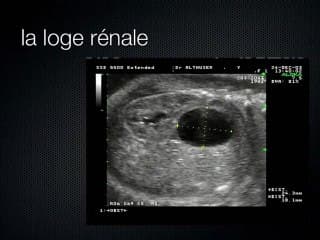

Brillante leçon de séméiologie de M ALTHUSER pour améliorer la pertinence du diagnostic d'une image anéchogène inhabituelle intra-abdominale. Ce diagnostic est aidé par une analyse systématisée qui tient compte notamment de la localisation, de l'appartenance, de la paroi, du contenu, de son éventuel péristaltisme, de la taille et du timing d'apparition de cette image. De nombreuses images de pathologies sont montrées : sténose duodénale, duplication digestive,kyste ovarien,obstruction du grêle, kyste méconial etc...